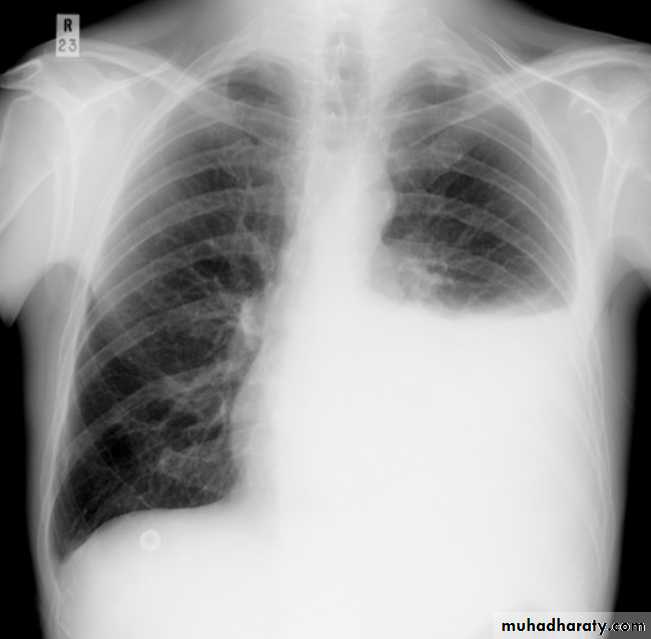

Pleural effusionPleural effusion tends to be used as a catch-all term denoting a collection of fluid within the pleural space. This can be further divided into exudates and transudates depending on the biochemical analysis of aspirated pleural fluid. Essentially it represents any pathological process which overwhelms the pleura's ability to reabsorb fluid.

Radiographic appearances

Plain radiographChest radiographs are the most commonly used examination to assess for presence of a pleural effusion, however it should be noted that on a routine erect chest x-ray as much as 250-600 ml of fluid is required before it becomes evident 6. A lateral decubitus film is most sensitive, able to identify even a small amount of fluid. At the other extreme, supine films can mask large quantities of fluid.

CXR (erect)

Both PA and AP erect films are insensitive to small amounts of fluid. Features include:

blunting of the costophrenic angle

blunting of the cardiophrenic angle

fluid within the horizontal or oblique fissures

eventually a meniscus will be seen, on frontal films seen laterally and gently sloping medially (note:

A subpulmonic effusion (infrapulmonary effusion) may be seen when there is previously established pulmonary disease, but can also be encountered in normal lungs , They are more common on the right, and usually unilateral

with large volume effusions, mediastinal shift occurs away from the effusion (note: if coexistent collapse dominates then mediastinal shift may occur towards the effusion)